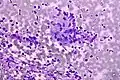

Colorectal adenocarcinoma. Field stain. Granuloma. Field stain.

Granuloma. Field stain.